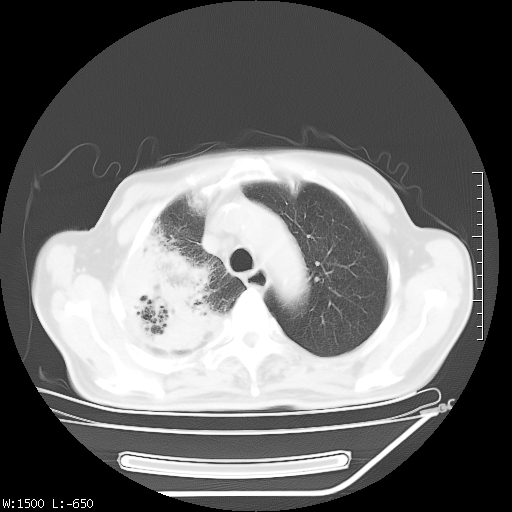

标题: CT23994:男、72、咳嗽、气短两月余,近来消瘦。 [打印本页]

标题: CT23994:男、72、咳嗽、气短两月余,近来消瘦。

右上肺实变,与胸膜关系密切,右肺容积缩小,隆突下淋巴结增大,考虑1 肺结核 2 肺癌

tb可能性大(双肺均可见片状密度增高灶,其内可见低密度空洞)。

右上肺大片状密度增高影,与胸膜关系密切,内见低密度透亮影,胸膜下可见三角形不张影,左下肺沿支气管走形结节影,纵膈内淋巴结显示。考虑结核并疤痕性不张可能性大,建议穿刺活检,排除肺泡癌。